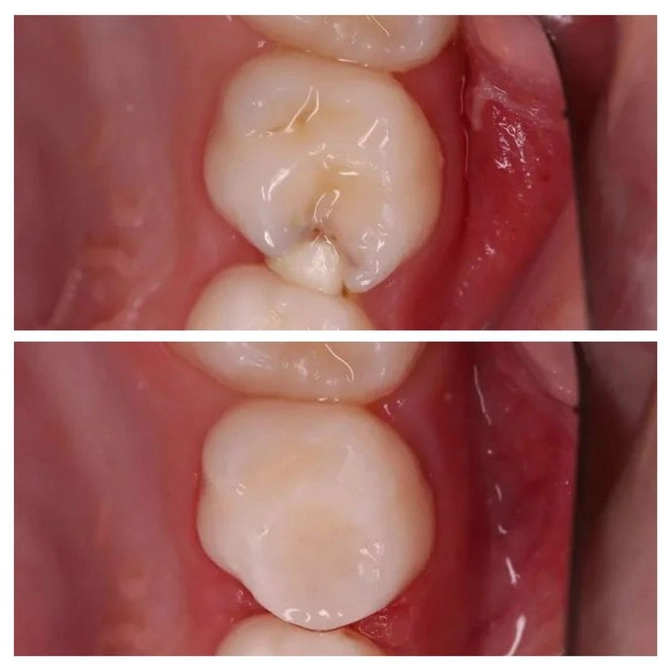

Замена несостоятельной пломбы

Зуб - "пятерка" - ранее пролечен от кариеса в государственной клинике.

Под пломбой началось повторное поражение зуба - вторичный кариес.

Такое бывает, когда цементная пломба дает усадку, нарушается прилегание ее к тканям зуба и внутрь попадают бактерии, вызывающие своей жизнедеятельностью разрушение зуба.

Темнота вокруг пломбы как раз указывает на то, что ткани стали разрушаться.

• Старую пломбу убрали;

• Кариес вычистили;

• Полость обработали;

• Зуб отреставрирован пломбировочным материалом;

• Эстетика и функциональность зуба восстановлены.